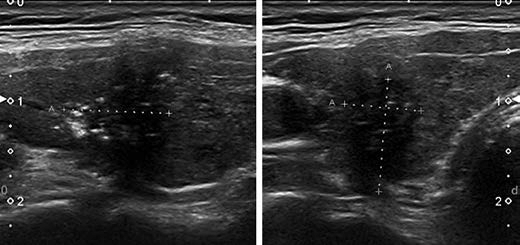

KTIRADS